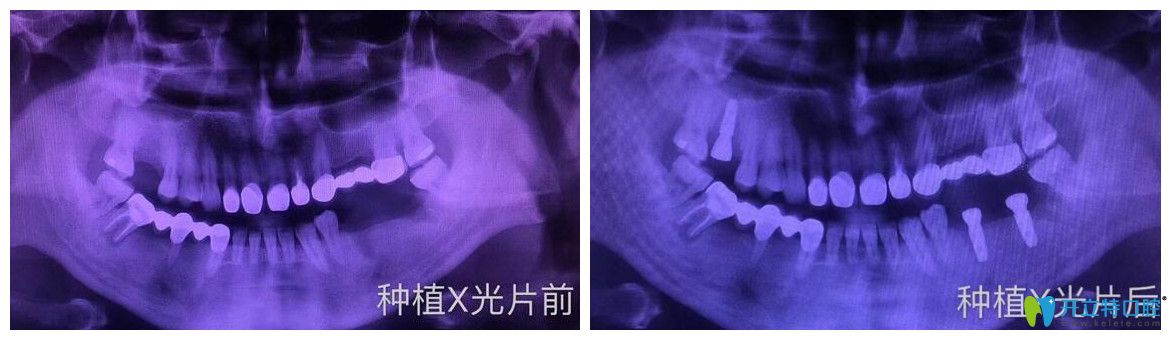

案例二:多顆牙缺失即刻種植案例

牙齒情況:種植前,牙齒意外松動脫落,平時吃東西特別不方便

種植技術(shù):即刻種植技術(shù)

逸盛口腔口腔多顆牙缺失即刻種植案例